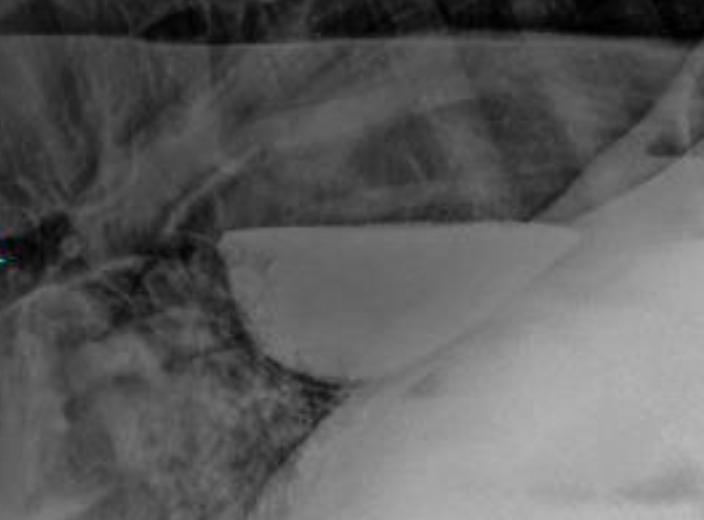

how are esophageal strictures diagnosed?

endoscopy, barium swallow studies

how is a esophageal diverticulum diagnosed?

barium swallow

how is megaesophagus diagnosed in horses?

presumptive diagnosis via clinical signs

definitive diagnosis via endoscopy, esophogram (barium swallow)